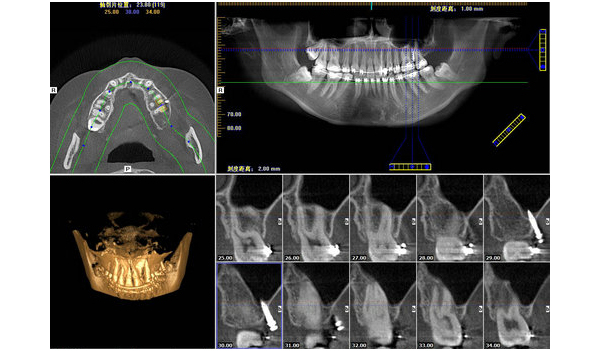

汕頭日?qǐng)?bào) | 恒牙“跑偏”長在牙根中間 醫(yī)生巧手為患者拔除2024-08